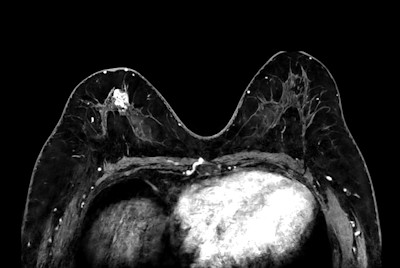

High quality Breast imaging with SmartSpeed Precise

Dynamic Breast imaging with SmartSpeed AI

Breast biopsy with dS Sentinelle Breast coil

Breast 3D and 4D imaging

Breast imaging with Compressed SENSE

Breast lesion